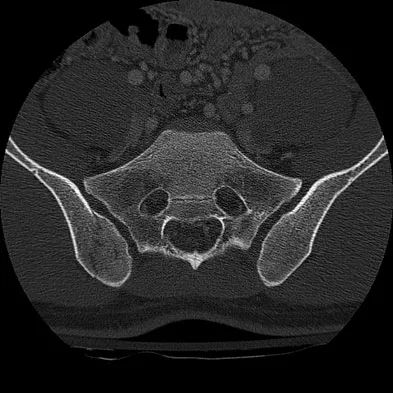

A 20-year-old man is brought to the emergency department after a high-speed motor vehicle accident. His initial blood pressure is 70/40 mm Hg. He is currently receiving intravenous fluids as well as blood. His Focused Assessment with Sonography for Trauma examination did not show any free fluid in his abdomen and his chest radiograph is unremarkable. An AP pelvis radiograph is shown in Figure 15. What is the next most appropriate step in the management of his pelvic injury?

A 30-year-old man who sustained a work-related injury 6 weeks ago reports persistent back and left-sided buttock pain that has been attributed to lumbar transverse process fractures. A pelvic radiograph and CT scans obtained 2 days ago are seen in Figures 17a through 17c. What is the best treatment for his injury?

A 36-year-old woman was injured in a train derailment. She has a significant open depressed skull fracture with active bleeding, a hemopneumothorax, and blood in the left upper quadrant and colic gutter by Focused Assessment with Sonography for Trauma (FAST) examination. Additionally, she has the pelvic injury seen on the CT scans in Figures 18a and 18b. The mortality rate for this patient approaches